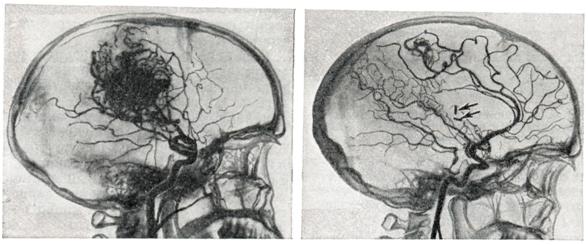

Диагноз.Появление перечисленных выше симптомов в молодом возрасте (чаще на 2—3-м десятилетии жизни) дает основание для предположения артерио-венозной аневризмы. Диагноз может быть поставлен лишь на основании всестороннего ангиографического исследования. Для выявления приводящих артерий и рано заполняющихся дренирующих вен необходима серийная ангиография с наибольшим числом снимков в первые 2—3 секунд. Лечение.Консервативное лечение является по существу симптоматическим и заключается в применении противосудорожных препаратов: фенобарбитал, дилантин и другие. При кровоизлияниях необходимо проведение коагулянтной и гипотензивной терапии. Лучевая терапия при артерио-венозных аневризмах неэффективна. Радикальным методом лечения является полное иссечение артерио-венозной аневризмы (рис. 4). Однако при большой распространенности аневризм и их расположении в глубинных, жизненно важных структурах мозга такая операция может оказаться невыполнимой. В подобных случаях могут применяться операции, уменьшающие приток крови к аневризме или приводящие к частичному выключению аневризмы,— окклюзия приводящих артерий, эмболизация артерио-венозной аневризмы и некоторые другие. Показания к той или иной операции должны быть строго индивидуальными; они определяются особенностями клинического течения, в частности количеством и тяжестью перенесенных кровоизлияний, локализацией, распространенностью аневризмы, характером ее кровоснабжения и опытом хирурга. В связи с совершенствованием техники операций, в частности широким использованием микроваскулярпой техники, показания к радикальному удалению артерио-венозных аневризм ставятся более широко, в том числе и при аневризмах, располагающихся в функционально важных зонах (речевой, двигательной). При радикальном удалении крупных, богато васкуляризируемых аневризм операцию следует начинать с выключения приводящих артерий. Благодаря этому уменьшается кровенаполнение аневризмы, а следовательно, меньше кровопотеря. При небольших поверхностно расположенных артерио-венозных аневризмах допустимо первоначальное выключение дренирующей вены; аневризма при этом наполняется кровью и более четко контурируется. Удаление аневризм, особенно расположенных в функционально важных областях, следует производить, выделяя сосудистый клубок по границе с мозгом, оставляя на поверхности аневризмы лишь тонкий слой измененного мозгового вещества. Важно при этом все время манипулировать вне пределов сосудистого клубка аневризмы, поскольку повреждение целостности ее сосудов приводит к сильному кровотечению, которое трудно остановить. Наличие внутримозговых гематом облегчает обнаружение аневризмы. Иногда гематомы как бы отслаивают часть аневризмы от мозга и тем самым упрощают ее удаление. При небольших глубоко расположенных аневризмах для облегчения их обнаружения во время операции могут быть использованы принципы стереотаксической нейрохирургии. Предварительно на основании расчетов по ангиограммам в область расположения аневризмы вводится направитель, по которому затем осуществляется подход к ней. При невозможности радикального удаления аневризмы может быть применено выключение приводящих артерий. Хотя этим путем обычно не удается достигнуть излечения и спустя некоторое время развиваются новые источники кровоснабжения артерио-венозной аневризмы, такая операция может привести к ослаблению кровотока в ней и уменьшить возможность повторных кровоизлияний. При больших, богато васкуляризированных аневризмах может быть осуществлена эмболизация сосудов аневризмы с помощью рентгеноконтрастных эмболов. С этой целью обычно используются различного размера пластиковые шарики, которые вводят через обнаженную на шее сонную (иногда вертебральную) артерию. В связи с резким ускорением тока крови в аневризме эмболы устремляются в ее сосуды. Таким образом иногда удается выключить из кровообращения значительную часть артерио-венозной аневризмы (рис. 5). Выполнение подобной операции требует точных представлений о характере кровоснабжения аневризмы, о диаметре, месте отхождения приводящих артерий и прочего. Каждый этап операции нужно контролировать повторным ангиографическим исследованием. Несоблюдение этих предосторожностей может привести к попаданию эмболов в нормальные сосуды мозга. Для направленного выключения сосудов, кровоснабжающих аневризму, а также для лечения других сосудистых поражений мозга (каротидпокавернозные соустья, некрые формы артериальных аневризм) применяют так называемые ангиотаксические операции. Смысл этих операций заключается в том, что подход к пораженному участку осуществляется по кровеносному руслу внутри просвета сосуда. С этой целью используют специальные катетеры, снабженные окклюзирующим баллончиком (Ф. А. Сербиненко, 1971). Такой катетер может быть направленно введен в приводящий сосуд артерио-венозной аневризмы посредством пункции сонной артерии на шее. Конструкция катетера позволяет произвести окклюзию сосуда, оставив в артерии баллончик, заполненный быстротвердеющим пластическим веществом, а катетер извлечь (рис. 6). Делаются попытки хирургического лечения артерио-венозных аневризм путем их замораживания с помощью жидкого азота. При аневризмах большой вены мозга, вызывающих окклюзию путей цереброспинальной жидкости, если нет условий для их удаления, возникают показания для разгрузочной операции с отведением цереброспинальной жидкости из желудочков мозга в венозное русло (вентрикуло-аурикулостомия). При тотальном удалении артерио-венозной аневризмы полностью исчезает опасность повторных кровоизлияний, прекращаются или становятся реже эпилептические припадки. Наступает нормализация кровообращения в головном мозге: при контрольном ангиографическом исследовании отмечается нормализация просвета ранее расширенных артерий, не заполняются дренирующие вены, лучше контрастируются сосуды областей мозга, прилегавших к аневризме. Летальность при тотальном удалении артерио-венозных аневризм колеблется в широких пределах и определяется прежде всего показаниями для хирургического лечения. По литературным данным, средняя послеоперационная летальность составляет приблизительно 10%, но при правильном определении показаний и использовании современных хирургических возможностей могут быть достигнуты лучшие результаты.